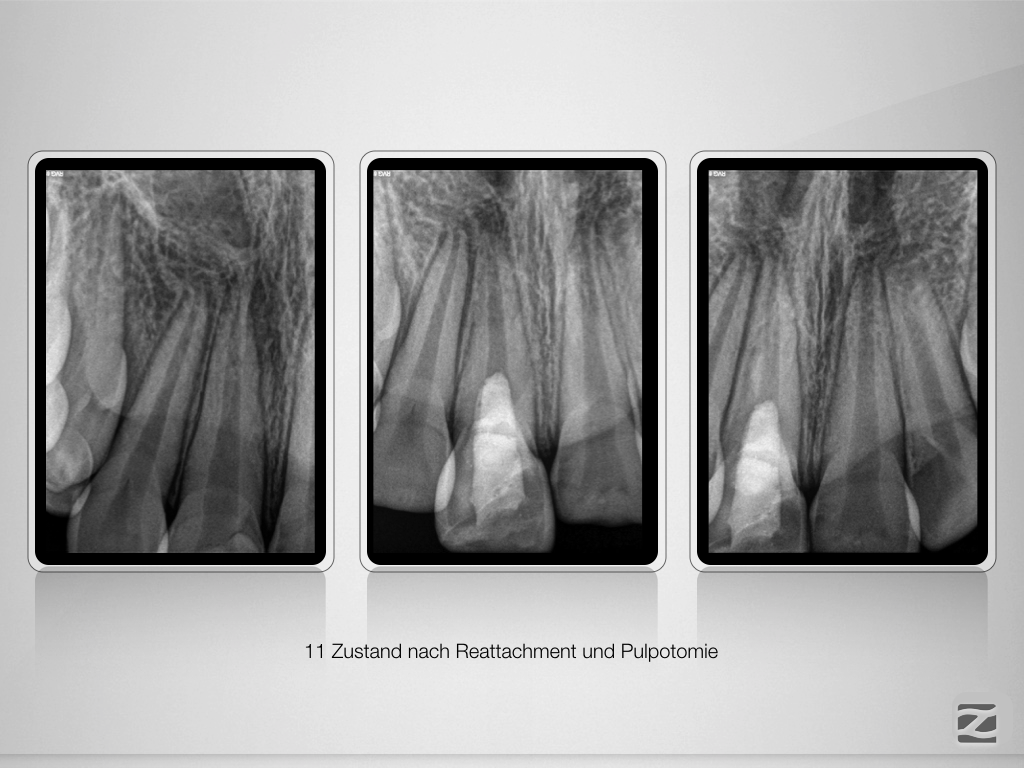

And the show goes on-Trauma, die Zweite.